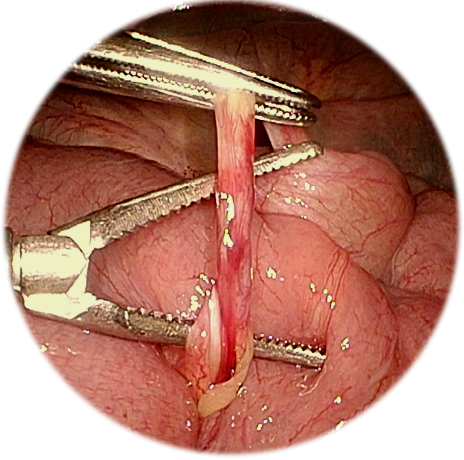

5.腹腔镜梅克尔憩室切除

腹腔镜梅克尔憩室切除术是针对症状性梅克尔憩室的现代微创金标准术式。梅克尔憩室作为胚胎期卵黄管残留最常见的先天性消化道畸形,其核心风险在于异位胃黏膜或胰腺组织的存在,可导致消化道出血、憩室炎、肠梗阻及肠套叠等严重并发症。